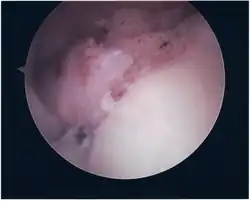

SLAP Tear

Repair of SLAP Tear

Arthroscopic SLAP Lesion (type 2) repair

Following inspection and determination of the extent of injury, the basic labrum repair is as follows.